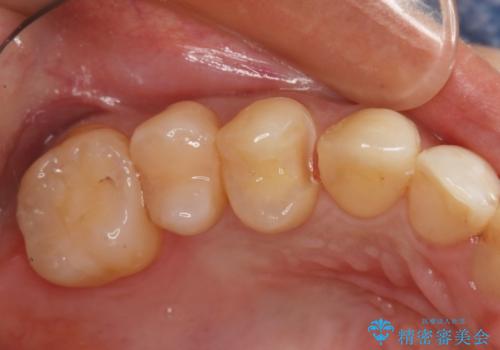

セラミックインレー

虫歯になった範囲が大きくなってくると削る範囲も比例して大きくなります。ある一定以上の大きさや範囲になった時の治療法に「インレー」というものがあり、保険の範囲では銀歯かプラスチック(適用条件有り)が、自費ではセラミックやゴールドといった素材を選ぶことができます。

セラミックやゴールドは、素材自体の劣化が非常に少なく精度も高いため、治療費はかかりますが、やり直しになる可能性を限りなく低くすることができます。